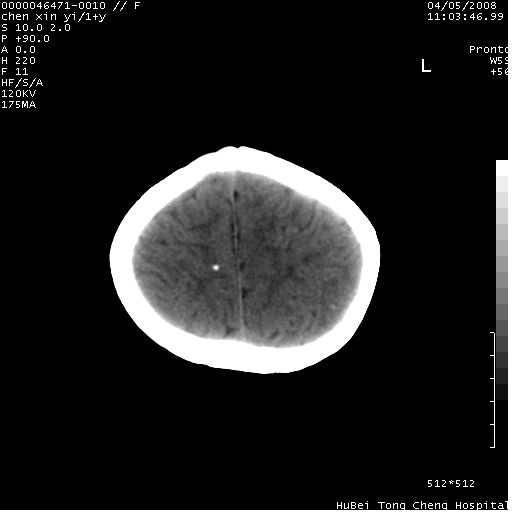

以下是引用zhangzhongshou在2008-4-9 12:54:00的发言:[br]请结合病史,有以下可能1、炎性肉芽肿钙化(含结核)2、寄生虫钙化(含脑囊虫)3、其他良性钙化性病变